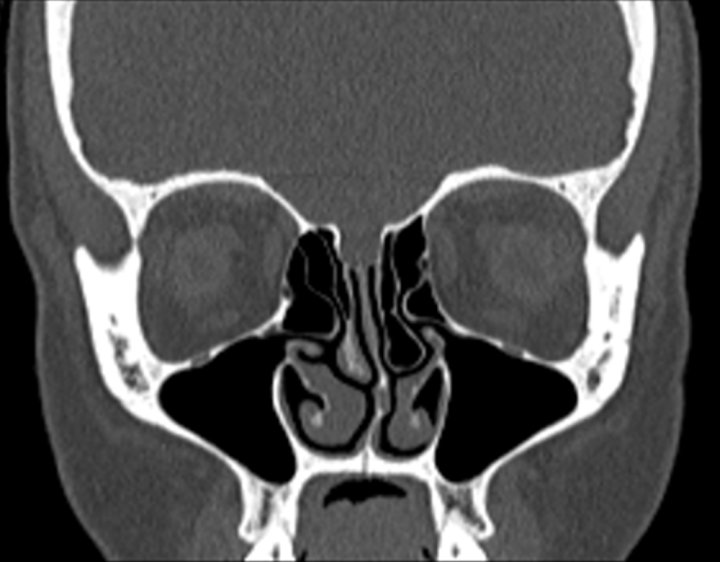

Click any image for labels.